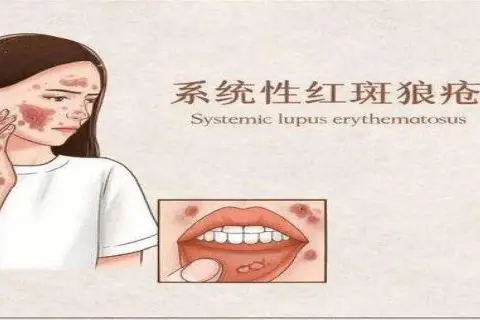

Conditions We Treat:cerebral palsy, autism, cerebellar atrophy, epilepsy, intractable epilepsy, cerebral hemorrhage, Parkinson's, Alzheimer's, sequelae of cerebral infarction, and various neurological disorders.